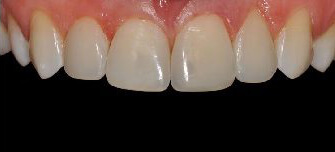

Probleem. Laiad hambavahed ja katkised hammaste servad.

Lahendus. 4 hamba esteetiline täitmine.